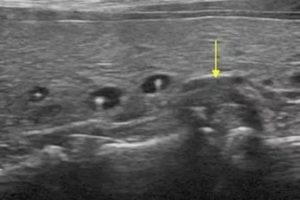

- Ультразвуковое обследование. При проведении УЗИ определяют диаметр, структуру уплотнений, отличают кисту в щитовидных долях от аденомы, струмы, аденокарциномы.

На первоначальном визите к эндокринологу, врач выясняет симптомы и проводит пальпацию. Определив наличие образования пальпаторно, врач направляет пациента на дифференциальную диагностику – УЗИ щитовидки. С помощью этого исследования определяется размер, структура и прочие характеристики новообразования.